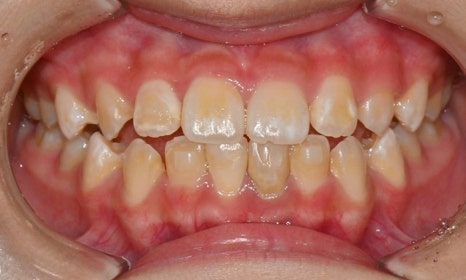

어태치먼트 주변의 착색 및 변색

첫번째 사진은 인비절라인 치료 중인 환자분 사진으로, 어태치먼트 주변으로 착색도 발생한 것을 확인할 수 있습니다. 두번째 사진은 어렸을 때 해외에서 인비절라인을 하다가 어태치먼트를 제거하지 않고 오래 유지를 하다가 내원해서 마무리 교정을 하기 위해 저희 병원에 내원한 환자 사진으로, 어태치먼트 주변이 노랗게 변색된 것을 확인할 수 있습니다.